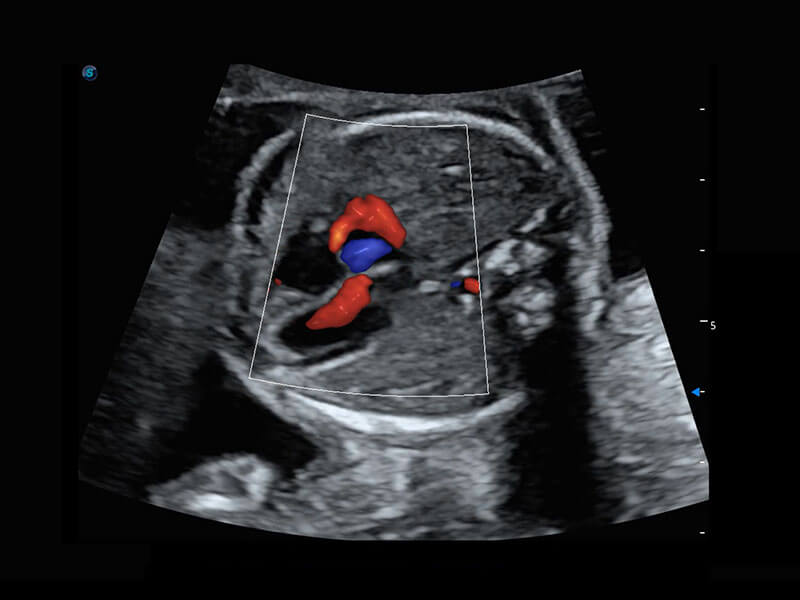

• 胎儿体循环

• 四腔心血流

P60搭载一系列胎儿心脏成像技术,实现精细的胎儿心脏评估。